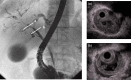

IgG4-related sclerosing cholangitis (IgG4-SC) is a distinct type of cholangitis frequently associated with autoimmune pancreatitis and currently recognized as a biliary manifestation of IgG4-related disease. Although clinical diagnostic criteria of IgG4-SC were established in 2012, differential diagnosis from primary sclerosing cholangitis and cholangiocarcinoma is sometimes difficult. Furthermore, no practical guidelines for IgG4-SC are available. Because the evidence level of most articles retrieved through searching the PubMed, Cochrane Library, and Igaku Chuo Zasshi databases was below C based on the systematic review evaluation system of clinical practice guidelines MINDS 2014, we developed consensus guidelines using the modified Delphi approach. Three committees (a guideline creating committee, an expert panelist committee for rating statements according to the modified Delphi method, and an evaluating committee) were organized. Eighteen clinical questions (CQs) with clinical statements were developed regarding diagnosis (14 CQs) and treatment (4 CQs). Recommendation levels for clinical statements were set using the modified Delphi approach. The guidelines explain methods for accurate diagnosis, and safe and appropriate treatment of IgG4-SC.